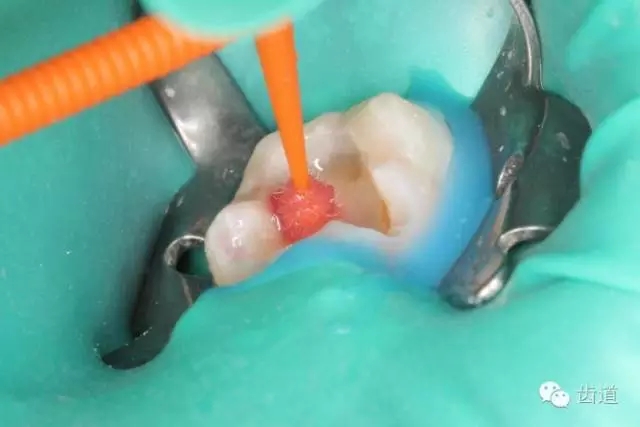

7. 3%次氯酸鈉浸泡髓腔5min

8. 浸泡后超聲清理髓腔,去除髓腔內(nèi)殘留牙髓組織